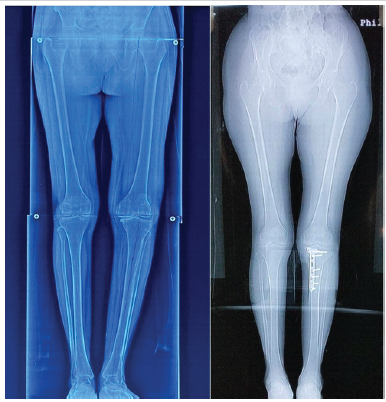

The post-operative alignment achieved in this study compares favorably with previously published literature, where most authors have reported a slight neutral to valgus correction following MOWHTO. et al. , Niemeyer et al. and Ghasemi et al. have demonstrated that maintaining correction close to the Fujisawa point—without excessive valgus—optimizes load redistribution while minimizing the risk of lateral compartment overload and subsequent progression of OA. We have maintained the weight-bearing axis through the Fujisawa point while avoiding incidences of non-union and lateral hinge fractures, supporting the adequacy of correction and reinforcing the importance of meticulous pre-operative planning to achieve biomechanically favorable outcomes [9,13,19]. [Fig 4]

Figure 4: Standing long-leg radiographs of the lower limbs. (a) Pre-operative radiograph showing varus mechanical axis deviation. (b) Post-operative radiograph demonstrating correction of the mechanical axis now passing through the Fujisawa point (left knee).